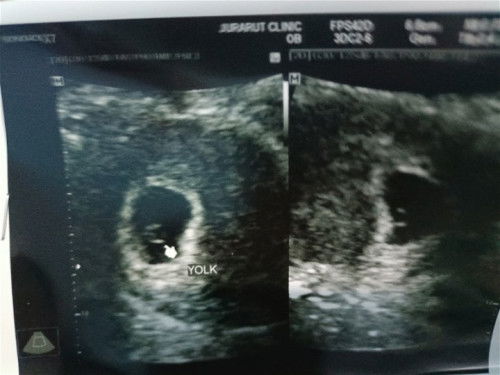

ตรวจเจอ6วันที่แล้ว ยังไม่ได้ฝากท้องค่ะ ถ้ามีอาการเจ็บท้องน้อยข้างขวากับซ้าย เจ็บหน่วงๆ บางทีก็จี๊ดด เป็นช่วงๆ เป็นมา3-4วันแล้วค่ะ พอไปตรวจที่ รพ. หมอบอกว่ากระเพาะปัสสาวะอักเสบ แต่ไปคลีนิกตรวจการตั้งครรภ์เขาคิดว่าน่าจะท้องนอกมดลูก #ใครมีอาการแบบนี้บ้างค่ะ เรากลัวมากเลยว่าจะท้องนอกมดลูก เพราะก่อนท้องทำงานยกงานหนัก ประจำเดือนไม่มา1เดือน ตรวจเลยขึ้นมา2ขีด